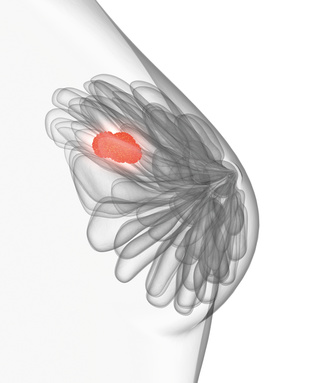

Zunächst - den Brustkrebs gibt es nicht. Allgemein wird damit eine bösartige Wucherung bezeichnet, die aus dem Brustdrüsengewebe hervorgeht.

Zunächst - den Brustkrebs gibt es nicht. Allgemein wird damit eine bösartige Wucherung bezeichnet, die aus dem Brustdrüsengewebe hervorgeht.

Das Brustdrüsengewebe besteht aus den Drüsenläppchen und den Milchgängen (siehe Aufbau der weiblichen Brust). Je nach seiner Herkunft hat der Tumor unterschiedliche Eigenschaften und Verhaltensmerkmale. Generell verhalten sich Tumore, die von den Milchdrüsenläppchen ausgehen, gutartiger als jene, die von den Milchgängen herrühren.

Zur genauen Bewertung des Tumors sind jedoch noch viele weitere Merkmale - wie etwa die Hormonrezeptoren - zu berücksichtigen, weshalb das Tumorgewebe vor der Behandlung einer intensiven Analyse durch den Pathologen unterzogen wird. Jeder Brustkrebs ist individuell, weshalb eine Behandlung auch immer individuell auf die betroffene Frau abgestimmt wird.

Das wichtigste Merkmal ist die Ausbreitung des Tumors (TMN-Klassifikation), die eng mit der Größe bei seiner Entdeckung zusammenhängt. Je kleiner der Tumor bei seiner Diagnose ist, desto besser und erfolgreicher sind seine Behandlungsmöglichkeiten.